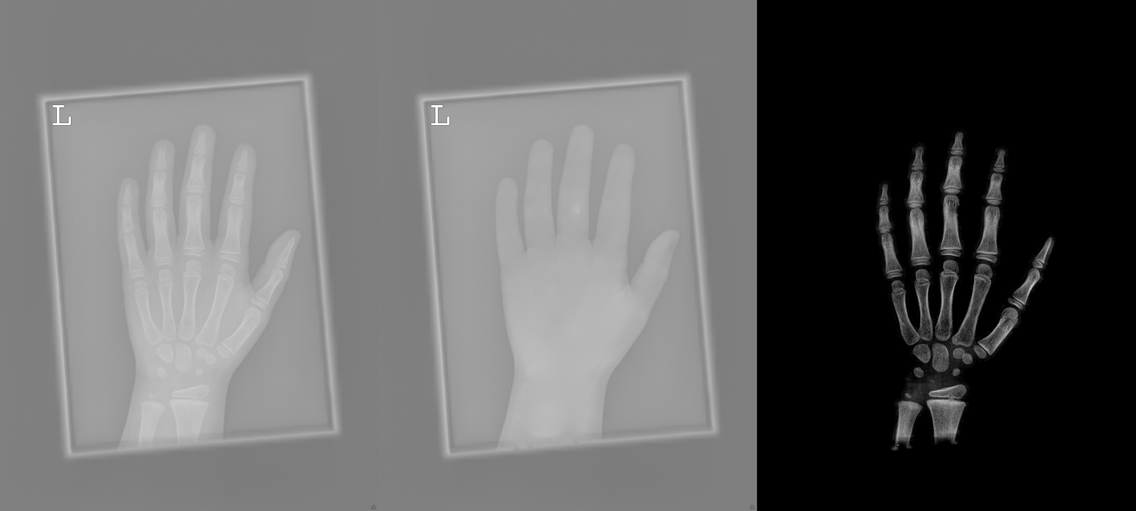

To tackle these problems, we propose to estimate the soft tissue image and bone image simultaneously without losing the linear relationship between image intensity and physical property of the imaging objects. Two examples from our method is shown in Fig. 1. The bone details are enhanced, which is theoretically guaranteed. The details of our method will be explained in later sections.

Several results from our method are shown in Fig. 7. The left column is the original input image. The right two columns are the soft tissue and bone image, respectively. It can be told that the soft tissue image is smooth as we assumed. Meanwhile, the bone image has better image contrast as desired. Moreover, our method can reach real-time performance on these X-ray images. The running time of our method on these images is reported in Table I.

In each panel of Fig. 10, the input image (left) is decomposed into soft tissue (middle) and bone image (right) by our method. Although we only show the first ten images from the data set, the results for the rest images are similar.

The bone images have better image contrast since the parameter is theoretically guaranteed. Such enhancement can also be directly told by radiologists. Such enhancement is good for bone diagnosis in practical applications.